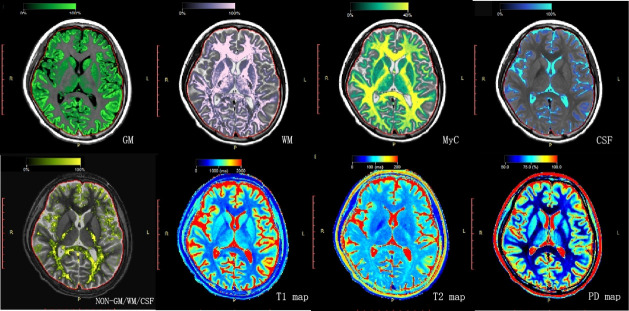

Methods: This prospective study enrolled patients with SLE and age, gender and education-matched healthy controls (HC). Study assessments included brain MRI using SyMRI and neuropsychological tests: Mini-Mental State Examination (MMSE), Montreal Cognitive Assessment (MoCA), Digit Span Test, Self-Rating Anxiety Scale and Self-Rating Depression Scale (SDS). SyMRI post-processing and Automated Anatomical Labeling were used for grey matter mapping. Correlation analysis was performed to assess the relationship between brain grey matter structural alterations and neuropsychological testing.

Results: 77 patients with SLE (57 non-neuropsychiatric SLE (non-NPSLE), 20 NPSLE) and 29 HC participants were enrolled. Patients with SLE showed reduced grey matter volume compared with HC (p<0.05). The NPSLE group exhibited more extensive increases in longitudinal (T1) and transverse (T2) relaxation times in grey matter than the non-NPSLE group (p<0.001). Proton density values were lower in patients with SLE (p<0.001). Lower brain parenchymal volume correlated with higher SLE Disease Activity Index (p<0.05). Lower MMSE/MoCA scores correlated with increased T1/T2 in the left medial cingulate and paracingulate gyri (p<0.05). Higher SDS scores correlated with increased T1/T2 in the left calcarine fissure and surrounding cortex (p<0.05). These changes were also linked to disease markers (C3, C4, immunoglobulin M, erythrocyte sedimentation rate) (p<0.05).

Conclusions: Grey matter alterations in patients with SLE correlate with cognitive impairment, depression and disease activity.